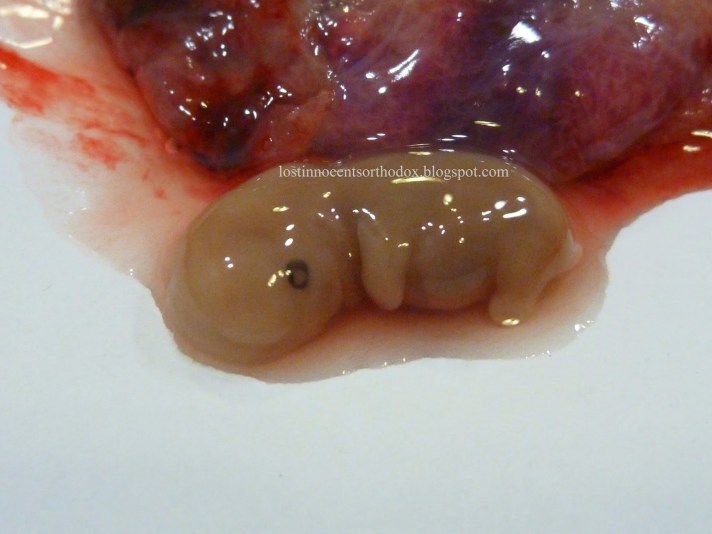

My baby, Demetrius (5 weeks, 5 days; delivered at 9 weeks)

And the photograph below is a textbook photo so you can see the detail: